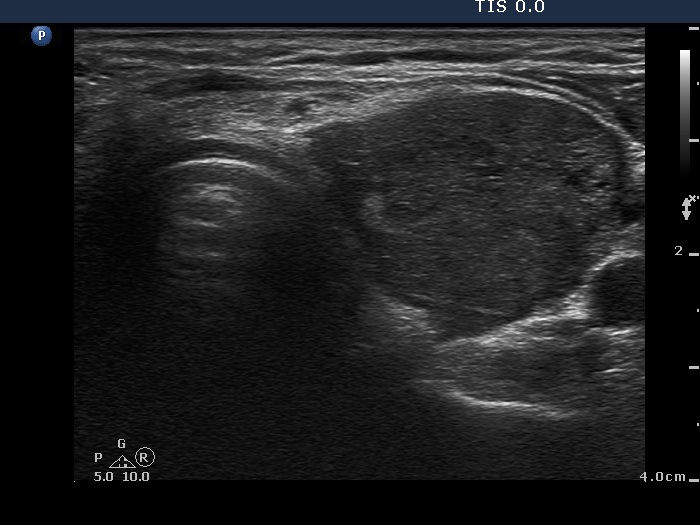

Ultrasonography: The right lobe was hypoechogenic, the left was moderately hypoechogenic. Both lobes were irregular in shape and were composed of several circumscribed areas surrounded with echonormal rim. The vascularization was significantly increased.

The sonographic pattern is specific. At first sight both lobes, particularly the right one seems to be nodular. First, the lobes are composed of a central hypoechogenic part surrounded with an echonormal rim, therefore it seems like the lobes were composed of a large hypoechogenic nodule. Second, connective tissue, perhaps a scar makes an impression in the ventral and in the dorsal part of the right and the left lobe, respectively. This makes an appearance as the lobes were composed of two nodules or one lesion with irregular lobulated and spiculated margins. In fact, the scar is responsible for the irregularities seen on the surface of the hypoechogenic mass, and regarding the hypoechogenic mass, the inclinations are the primary cause.